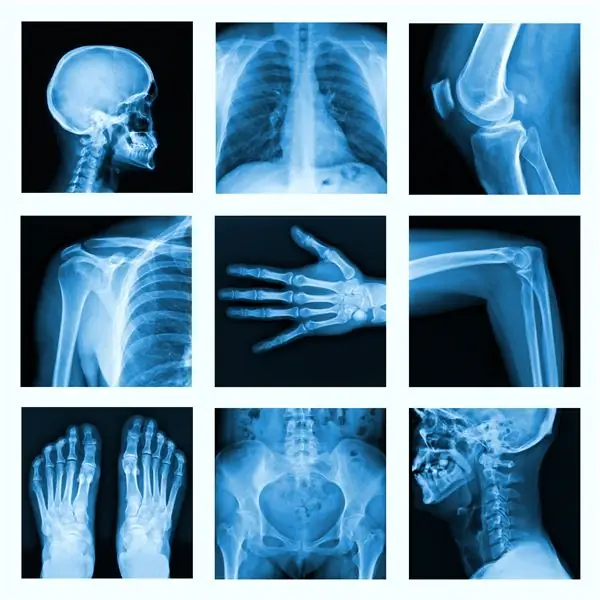

Коллаж из многих рентгеновских снимков в очень хорошем качестве

Дегенеративные заболевания часто поражают костную систему.